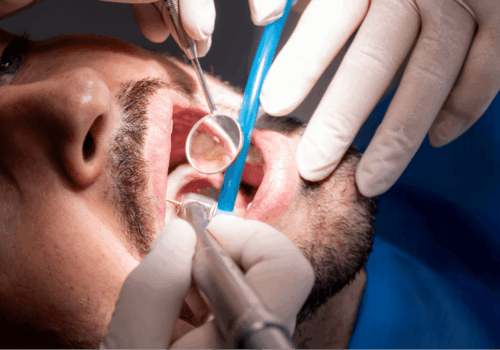

Trattamento:

Il trattamento di un trauma odontoiatrico varia in base alla gravità e alla tipologia del danno.

Può andare da un semplice controllo e monitoraggio a interventi complessi come:

- Ricostruzione con compositi

- Devitalizzazione (endodonzia)

- Chirurgia orale

- Reimpianto del dente

Importante: recupera sempre eventuali frammenti o denti avulsi e conservali in ambiente umido (latte, saliva, soluzione fisiologica o acqua) fino all’intervento.

Un intervento tempestivo è fondamentale per aumentare le possibilità di recupero del dente o dei tessuti coinvolti. In molti casi, la gestione del trauma è multidisciplinare e può coinvolgere la chirurgia orale, l’ortodonzia e nei pazienti giovani, la pedodonzia, allo studio Lazzaroni, fortunatamente, trovi tutte le competenze necessarie ad un pronto intervento. In tutti i casi, un’azione tempestiva può davvero fare la differenza, sarà tanto più importante – ove possibile – cercare eventuali frammenti o denti avulsi sul luogo del trauma e conservarli in ambiente umido: saliva, latte, soluzione fisiologica o acqua.